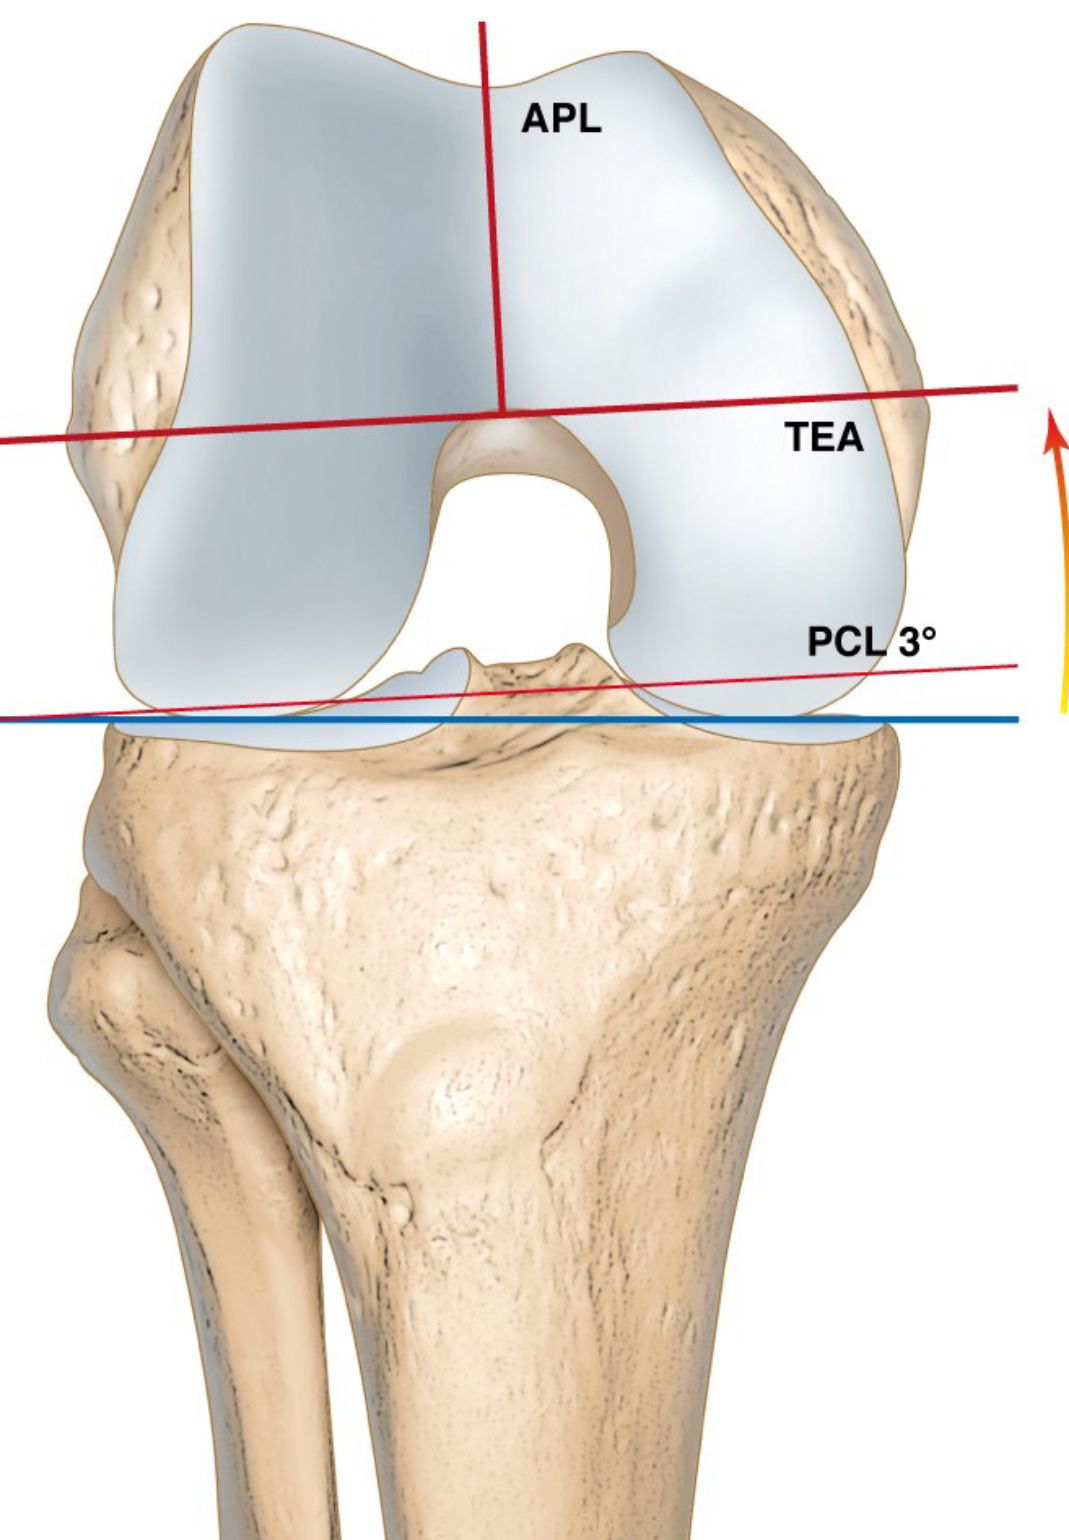

1.1. Femur first or measured resection

This technique was introduced by John Insall more than 40 years ago where the distal femur and tibia are cut perpendicular to the mechanical axis in 90° to gain a neutral frontal mechanical axis. The femur component is placed parallel to the transepicondylar axis (TEA) in the axial plane [1]. It is generally accepted that the TEA represents the best compromise for the flexion axis in TKA surgery [8]. This classical Insall technique remains still the standard femur rotational alignment for most surgeons until now [2]. (Fig 3).

For the natural knee it is well known that the femur flexion axis represents a very complex helical structure due to the asymmetric bones, menisci and both cruciate ligaments. For TKA surgery the transepicondylar axis (TEA) represents the best compromise for the knee flexion axis [2,6]. The problem with the TEA is, that intraoperative identification is difficult, and several studies have shown wide inter- and intraobserver variability [8]. Therefore, many other different landmarks had been described to reduce this problem and increase the accuracy to identify the TEA [2,7] (Fig 9). Most of TKA instruments still use the most prominent point of both posterior condyles (posterior condylar axis) as reproducible landmarks to set femur rotation.

For many decades standardized 3° ER were used to bring the femur component parallel to the TEA by referencing to the posterior condylar axis. The new 3-D mega data clearly demonstrated that in knees planned for TKA surgery a wide range of internal rotation (minus 3 ER to 11° IR) of the posterior condylar axis to the TEA exists (Fig 10) [27,31,32].

For valgus knees it was well known that due to the possible hypoplastic lateral condyle the posterior condylar axis might be more than 3° of IR and many surgeons routinely used 5° ER to the TEA in valgus knees. A wide range from 3° to 12° of IR of the posterior condylar axis to the TEA could be shown with the new 3-D mega data for valgus knees also [32]. For varus knees it was long assumed that 3° of ER will fit for rotational alignment. Now we know that even in varus knees axial plane femur deformities are possible and show a wide range from 3° of ER (worn out posterior medial condyle) to 9° of IR (hyperplastic medial condyle) from the posterior condylar axis to the TEA (Fig 11) [32]. 32 % of femur needs more than 3-5° ER (6-11), whereas 10 % less than 3° ER (IR 3 to ER 2°) [31].